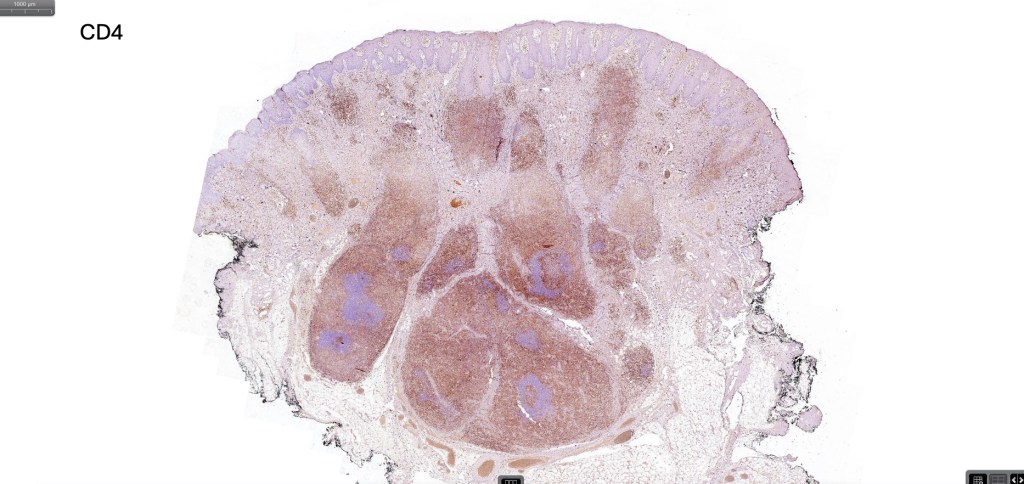

Histological features

•Follicular infiltration by atypical lymphocytes & Sézary cells